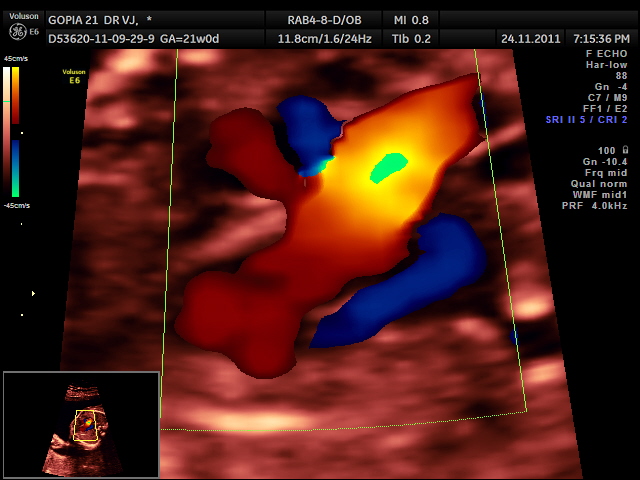

colour doppler showed

a 3 d reconstruction is given below